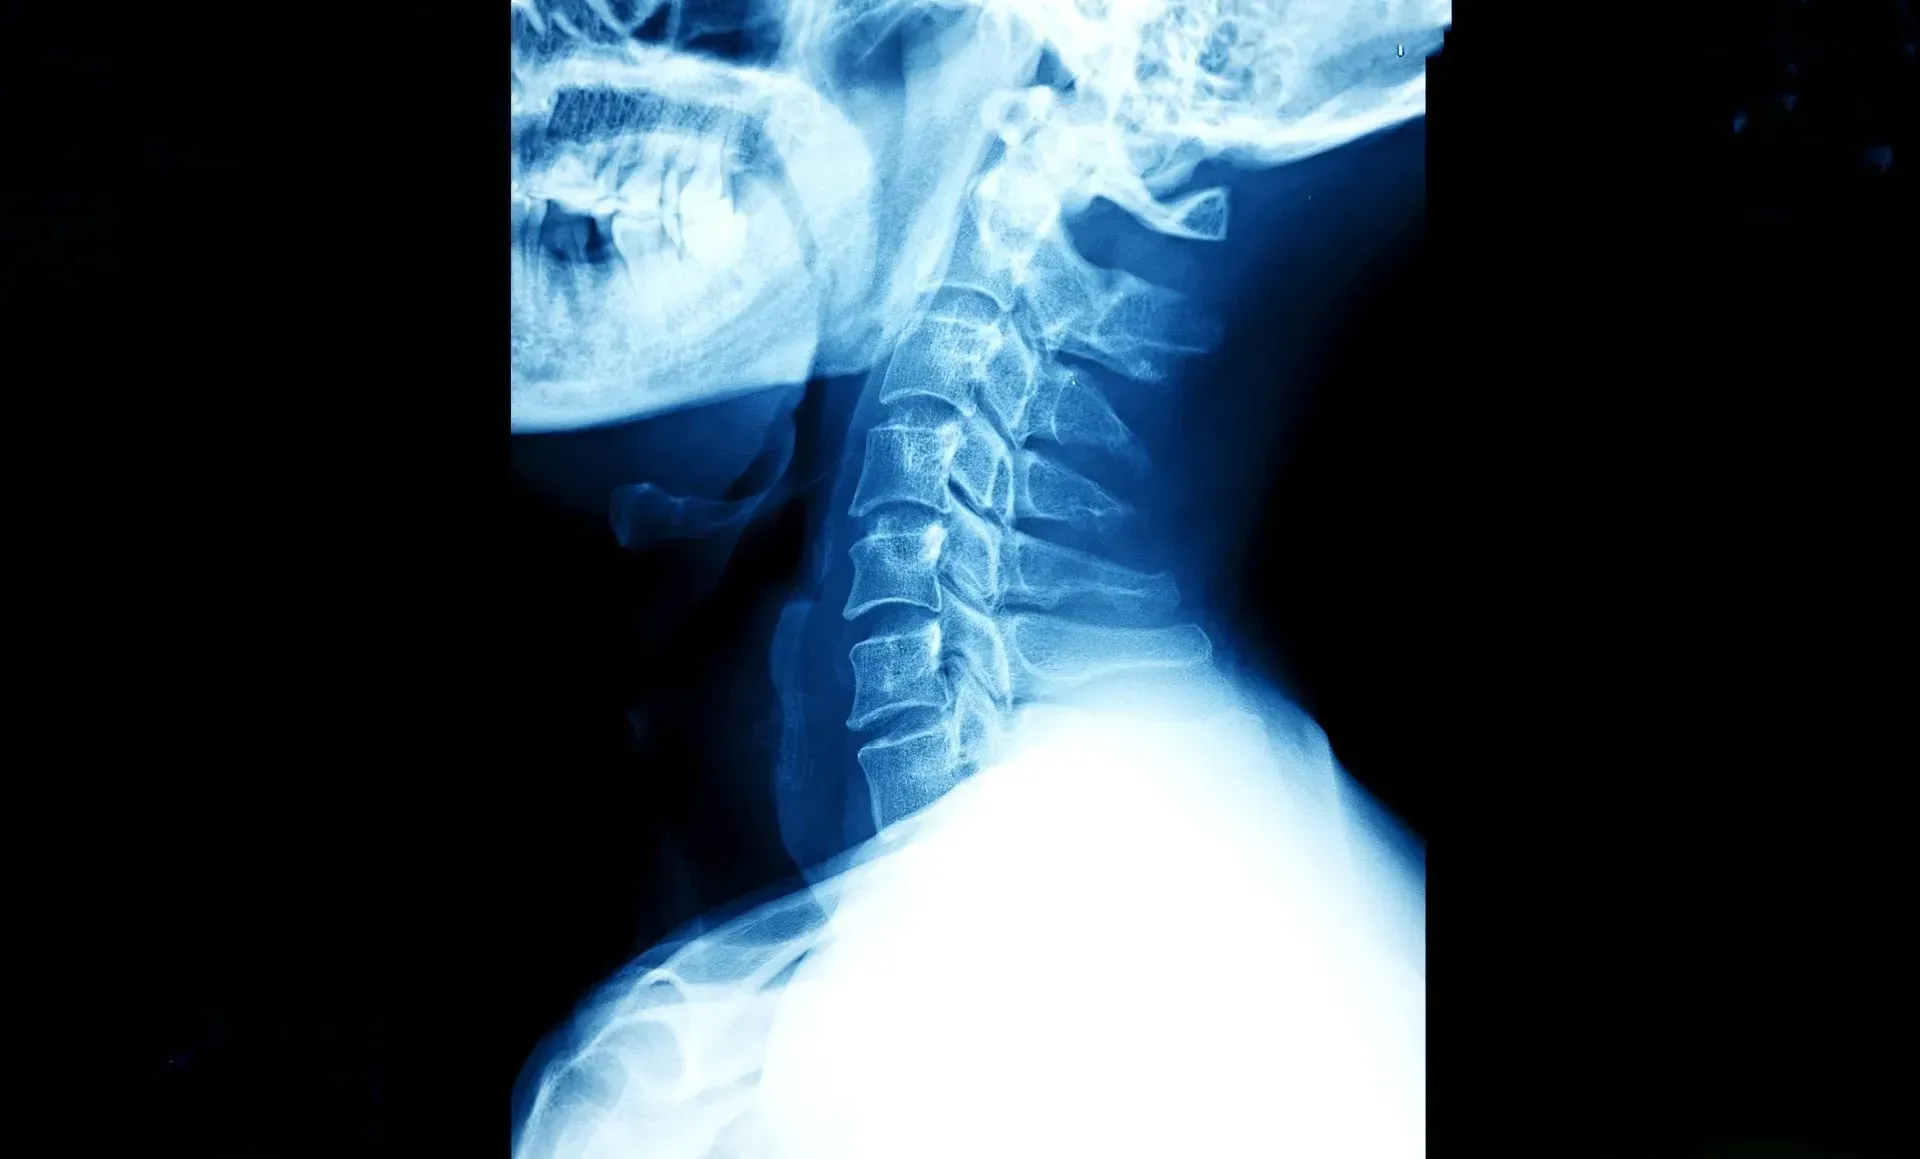

"To see is to know," and with digital radiology, the medical team gains unparalleled insights into a patient's condition. Gone are the days of traditional X-ray films, as digital radiography revolutionizes the way images are captured and analyzed. The technology utilizes electronic sensors to capture X-ray images, which are then transmitted to a computer, rendering clear and detailed pictures of the internal structures of the body.

With digital radiography, the image quality is exceptional, providing the chiropractic team with clear, high-resolution images for precise diagnosis. The ability to magnify and manipulate the images enables chiropractors to focus on specific areas of concern, ensuring a comprehensive assessment of the patient's health. Additionally, the digital format simplifies the sharing of results with other healthcare providers, facilitating a collaborative approach to patient care.

Digital radiography offers a versatile diagnostic approach, enabling Back 2 Health Chiropractic Center to address a wide range of health conditions. From assessing spinal misalignments to evaluating joint health and bone integrity, the digital radiography system caters to various chiropractic needs. This versatility enhances the center's ability to develop personalized treatment plans, ensuring optimal outcomes for each patient.